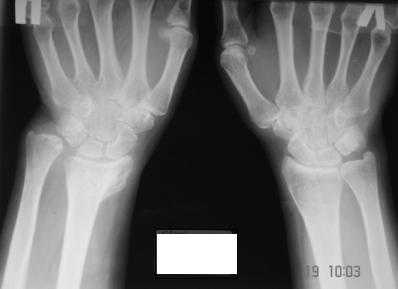

Обратилась женщина, 55 лет. Травма 3 месяца назад, лечилась по месту жительства (Рис.1). Косорукость, боли, ограничение движений. Досняли - рис.2-6. Хотелось-бы услышать мнения  об объеме операции.

Имя     : 3.JPG